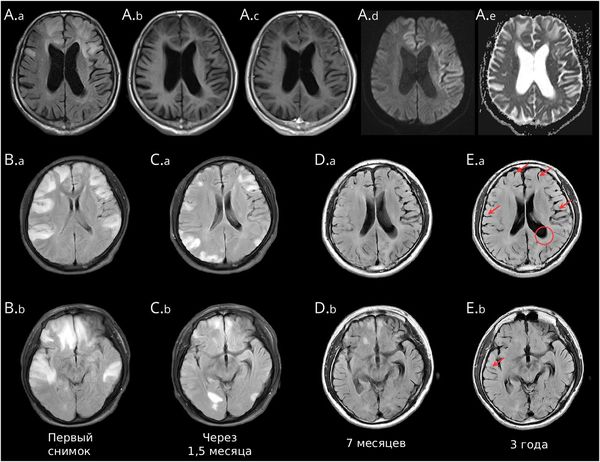

Deng B., Cai M., Qiu Y., Liu X. et al. MRI Characteristics of Autoimmune Encephalitis With Autoantibodies to GABAA Receptor: A Case Series // Neurol Neuroimmunol Neuroinflamm. — 2022. — № 3. — Р. e1158. ссылка